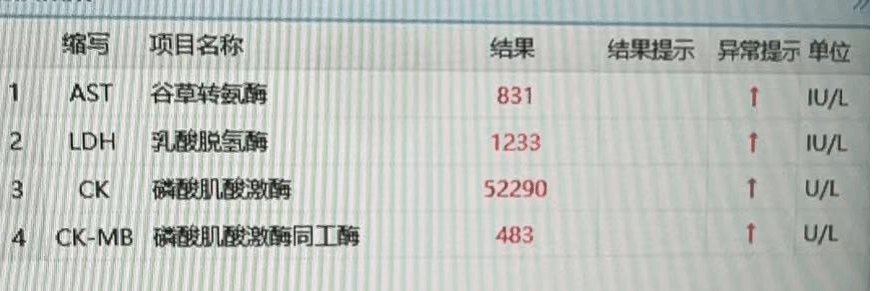

由于患者病情复杂,诊疗过程惊险环生,患者长期房颤病史,合并高血压、哮喘等多种基础疾病,术后循环不稳定,并出现了胸腔积液,肾功能不全,茶色尿液,尿量24小时约500ml,心衰情况加重,房颤心律不齐,监护仪心率170次/分,检验指标频繁上报危急值,术后第一天磷酸肌酸激酶升至57898U/L,高敏肌钙蛋白41pg/ml。术前患侧肢体肌肉有部分坏死情况,术后肢体出现张力性水泡、高度肿胀,病情一度危重。血管外科团队放弃了假期,全力救治患者,与多学科专家联合会诊,制定了详细的术后管理方案,持续血液净化(CRRT)、胸腔穿刺放胸水、抗凝、抗感染治疗及营养支持等综合救治措施。经过大年三十--初七八天的紧急救治,患者的下肢温度逐渐回升,疼痛感明显缓解,避免了因急性缺血导致的肢体坏死和截肢风险。真正的做到了患者的诉求“保肢保命”转危为安。患者生命体征趋于平稳,肾功能也逐渐恢复,现已康复出院。此次救治不仅体现了医院多学科协作的高效性,也展现了医护人员在危重症救治中的专业水平和责任担当。

患者各项检验指标均处于危急状态